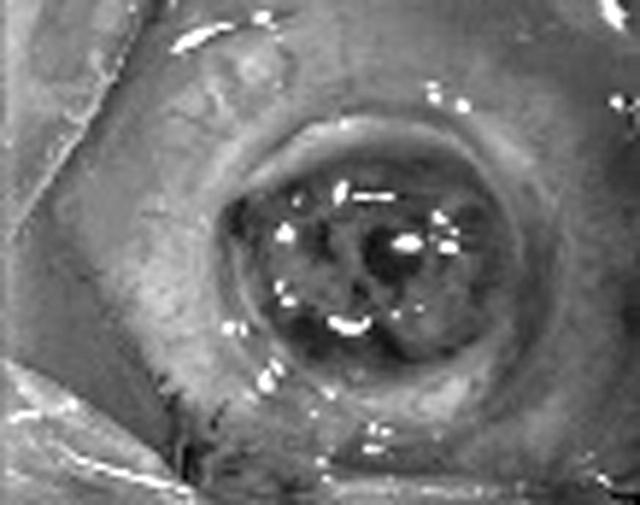

Figure 1.

Intraoperative clinical photograph of congenital hereditary endothelial dystrophy showing microvitreoretinal entry.

Figure 2.

Clinical photograph after completion of keratoplasty.